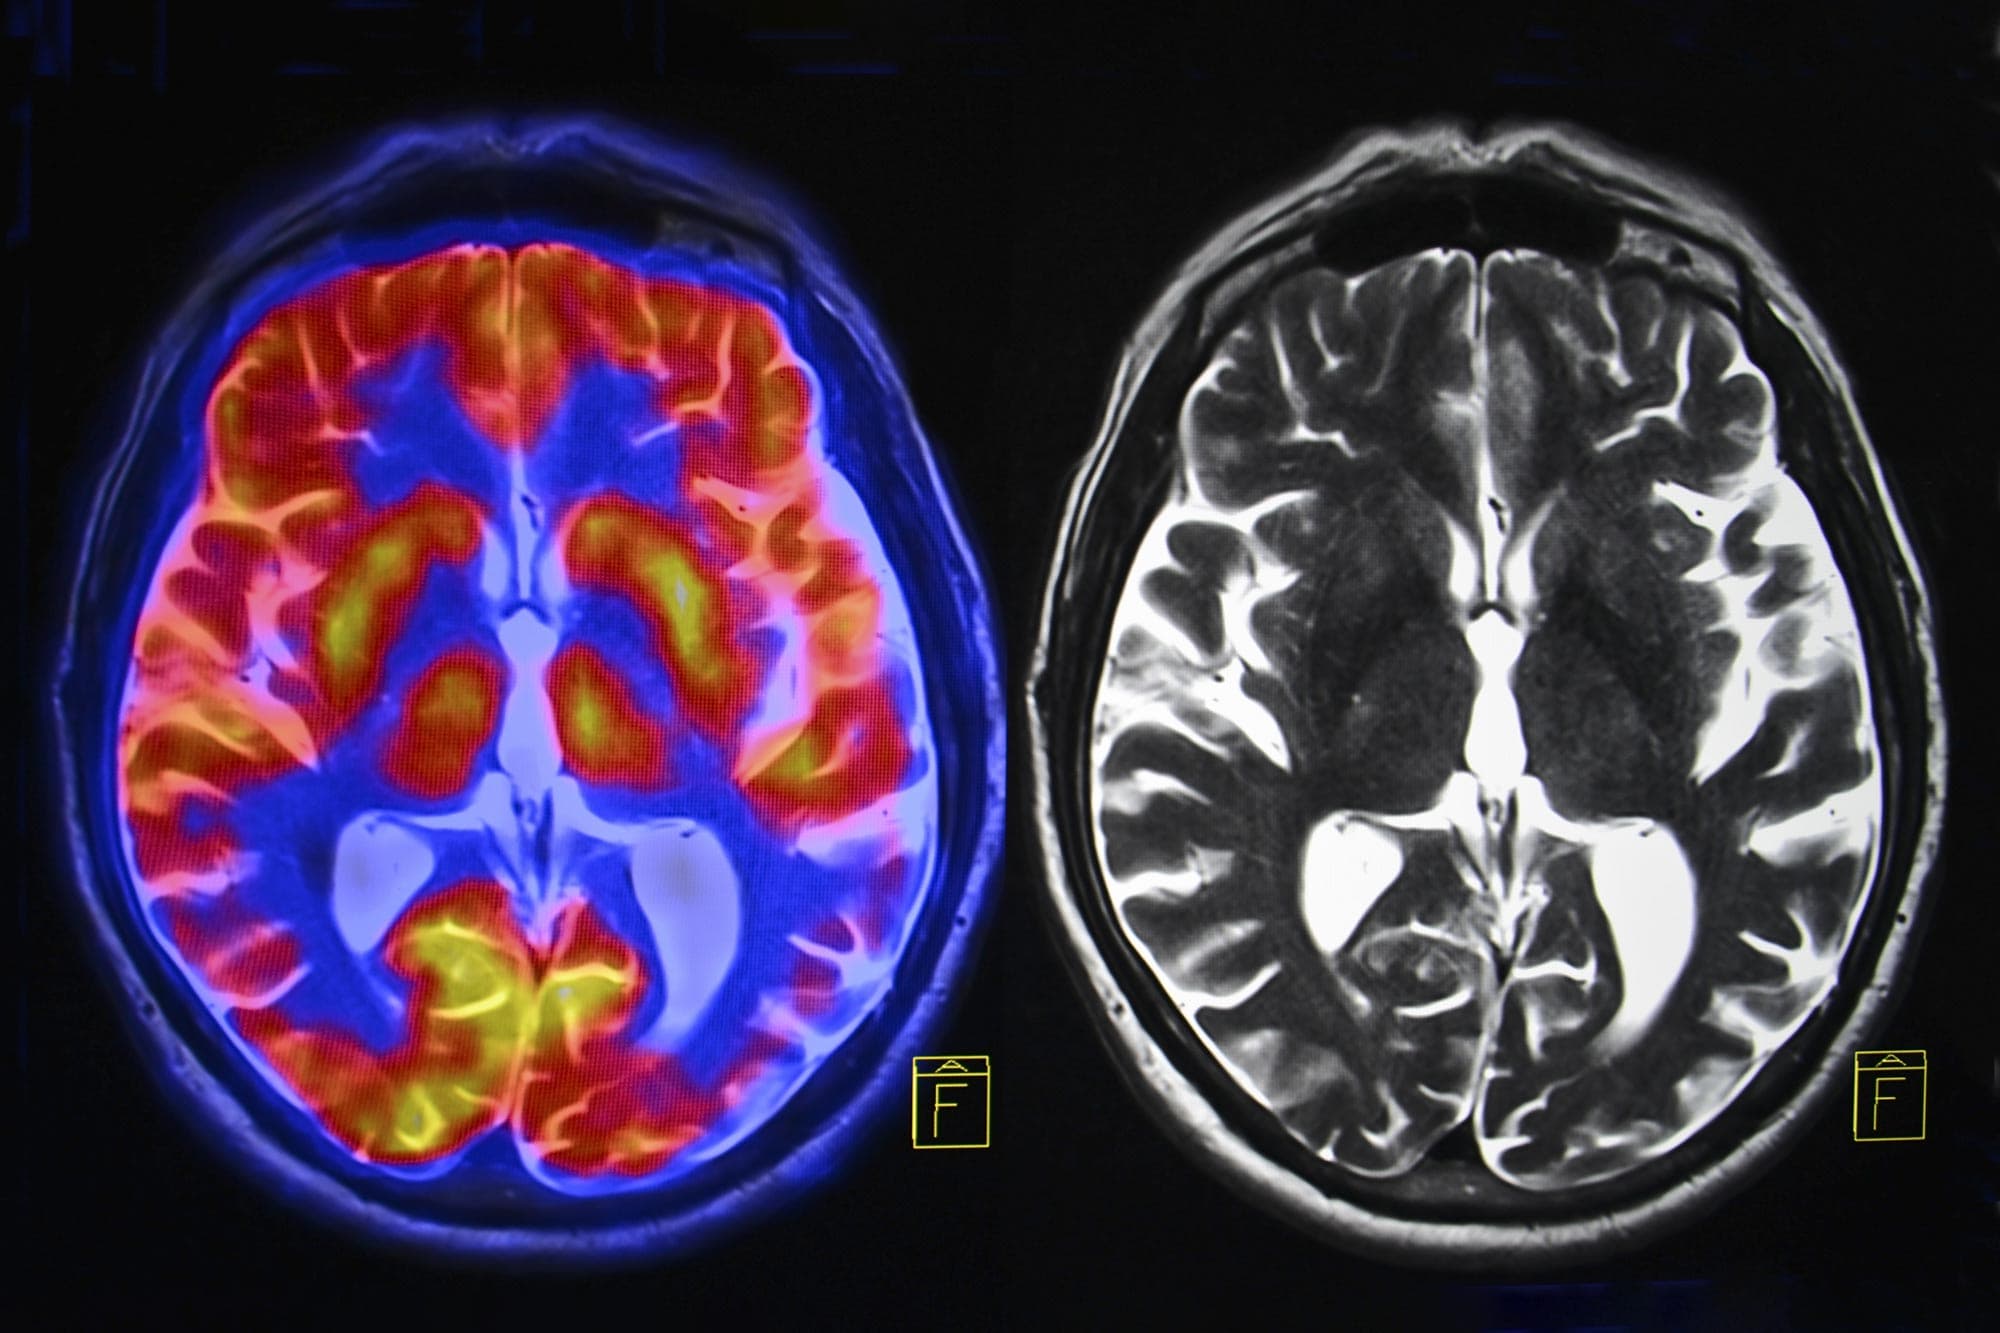

Research from the University of Cambridge, led by Professor Barbara Sahakian, reveals that the drop in oestrogen during menopause causes a direct loss of grey matter in brain regions critical for memory and emotion. This finding sheds light on a grim statistic: women account for nearly two-thirds of all dementia cases globally. In East Africa, where dementia prevalence among those over 60 is estimated at 4.2%, this link signals a looming public health crisis as life expectancy rises.

The study utilized advanced brain scans to observe the "energy crisis" that occurs in the female brain during midlife. As oestrogen levels crash, the brain is deprived of a key neuroprotective element, leading to inflammation and the accumulation of amyloid plaques—the hallmarks of Alzheimer's.